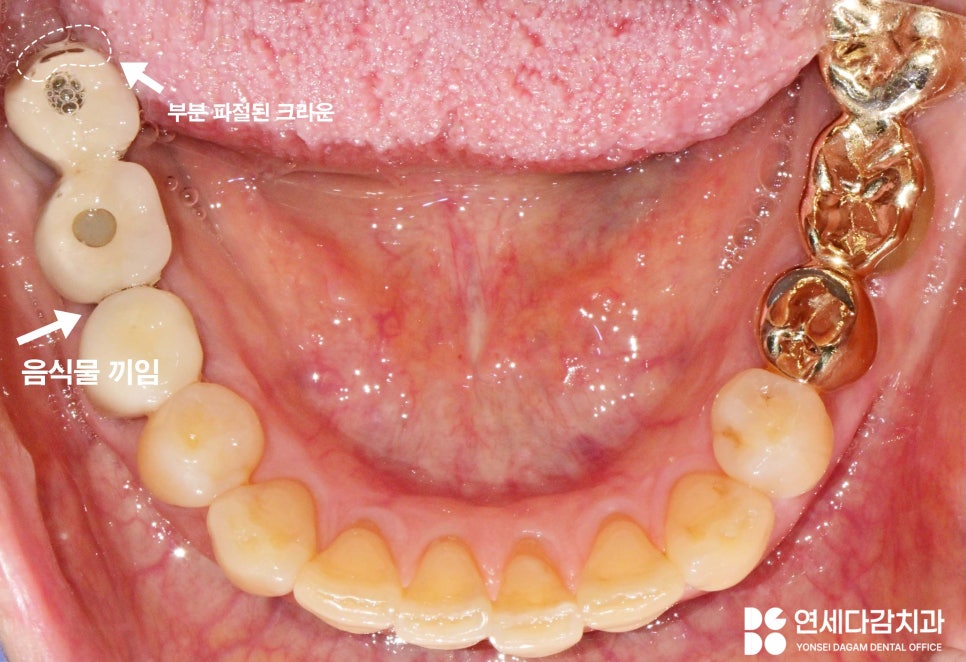

오래된 보철의 큰 특징은

치아 사이 긴밀함이 떨어져

음식물이 이 사이에 많이 끼고,

저작기능이 떨어진다는 점입니다.

문정동 치과 에서

15년 이상 된 보철을 살펴보면

많이 닳고 깨진 모습을

볼 수 있습니다.